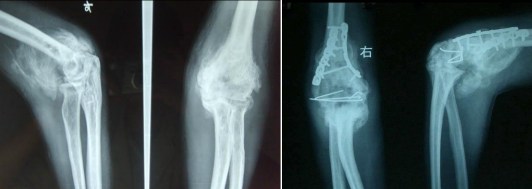

· 保守治疗:骨块成熟前(约1年),以消炎、镇痛、维持无痛活动为主。

· 手术治疗:仅用于骨块完全成熟且严重影响功能时。术后需立即联合药物或放疗预防复发,并积极康复。